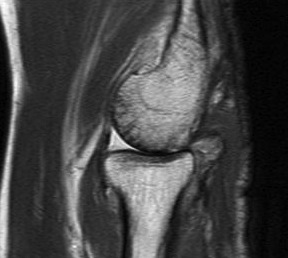

MRI

Useful in detecting early chondral damage

MRI chondral damage radiocapitella joint Chondral thinning anterior ulnohumeral joint

Chondral changes in the radiocapitellar and ulnohumeral joint